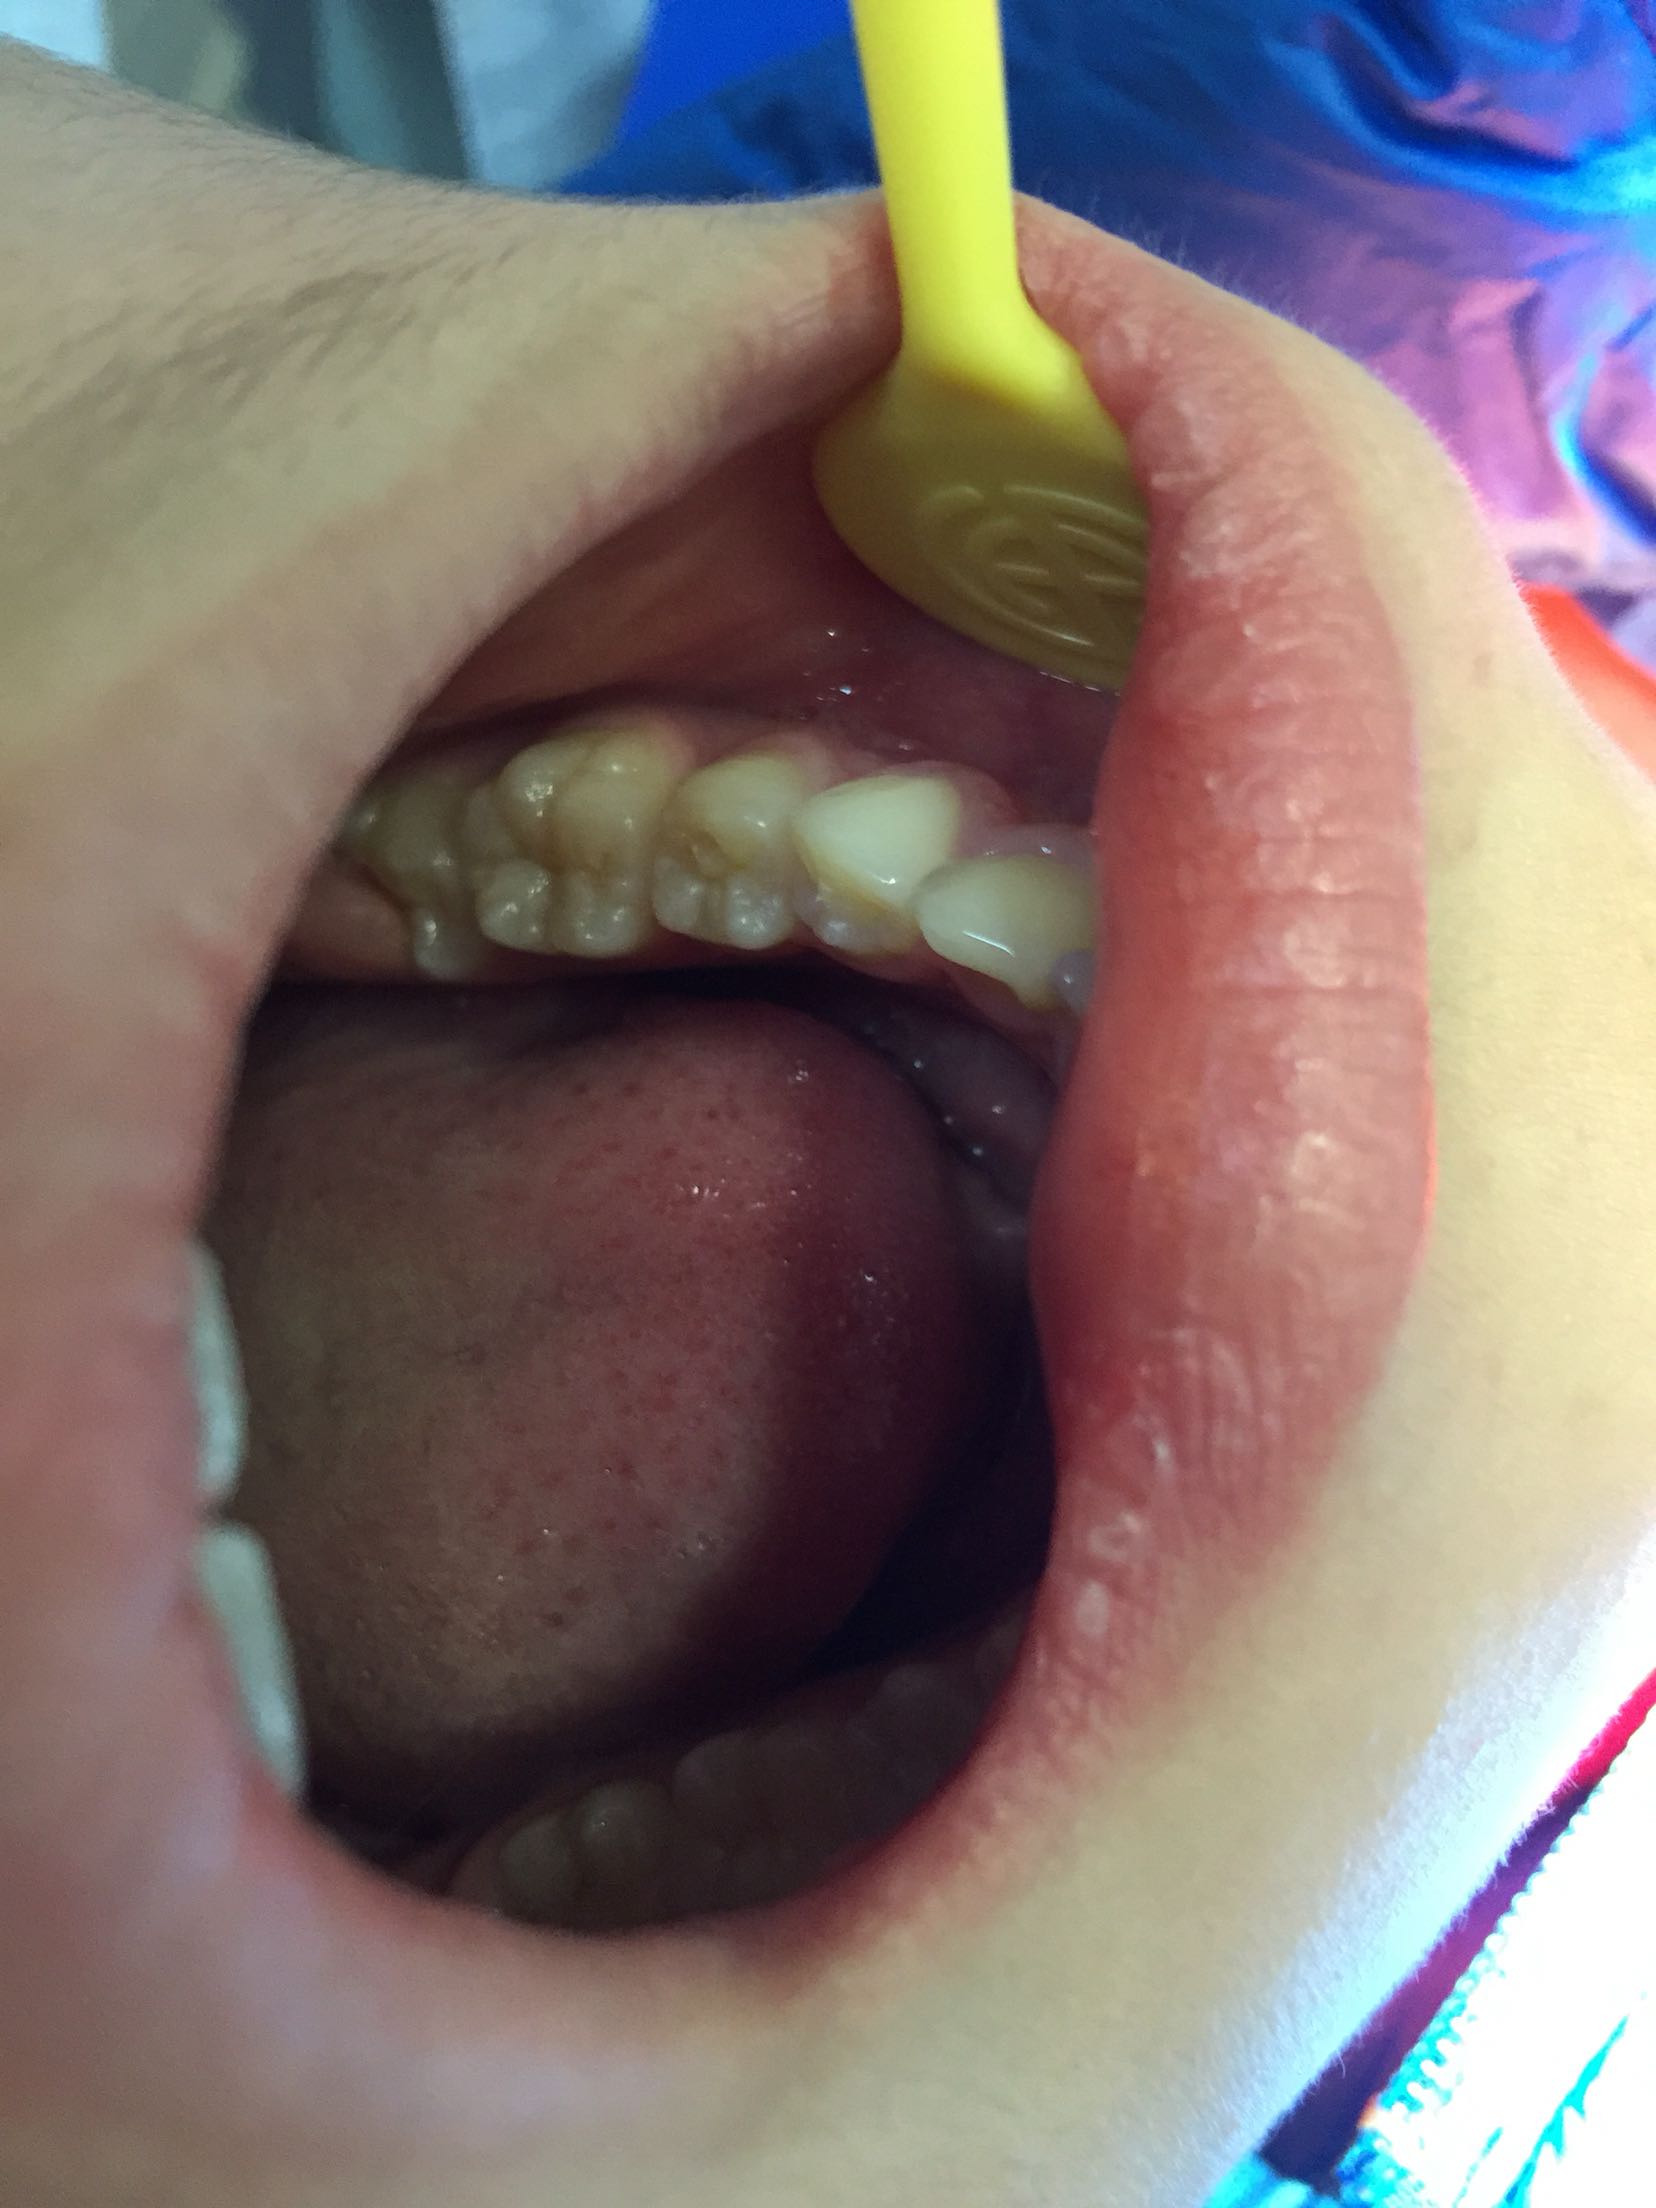

检查:35未见明显龋坏,合面可见畸形中央尖磨损,叩诊(++),松动度l度,牙龈未见明显红肿,冷诊(-)。 辅查:X线片示:35根尖基本发育完成,根尖区低密度影像。